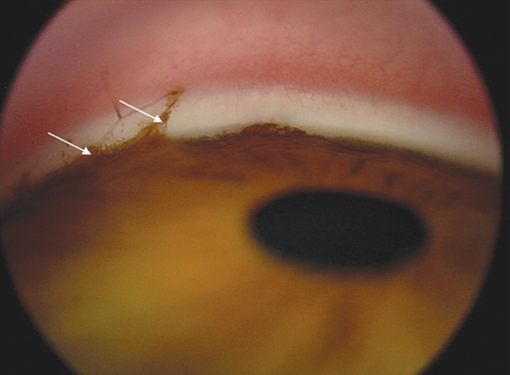

Аналогичные изменения выявлялись и при 3-й степени рубцовой фазы РН — 8 глаз (80 %) (рис. 6). Четвёртая степень характеризовалась в основном дисгенезом УПК — 4 глаза (80 %), в то же время отмечался единичный случай дисгенеза с более грубыми анатомическими изменениями в виде иридокорнеальных сращений, приводящих к уменьшению глубины передней камеры и её деформации (рис. 7), которые преобладали при 5-й, терминальной степени (рис. 8).

Рис. 8. Изображение угла передней камеры глаза ребёнка, 13 лет, с рубцовой ретинопатией 5-й степени, глаукомой (белыми стрелками показана зона иридокорнеального сращения, атрофия радужки)

Fig. 8. Image of the anterior chamber angle of the eye of a 13 y.o. child with degree 5 cicatrical ROP and glaucoma (white arrows show the area of the iridocorneal adhesion, iris atrophy)